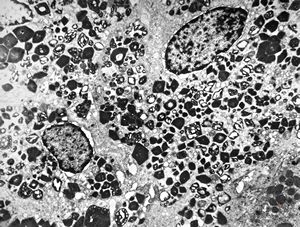

M,16y. | lipofuscin - hyperbilirubinaemia - Gilbert or Dubin-Johnson syndrome

M,17y. | lipofuscin - hyperbilirubinaemia - Gilbert or Dubin-Johnson syndrome

M,17y. | hyperbilirubinaemia - lipofuscin - Gilbert or Dubin-Johnson syndrome

F,12y. | lipofuscin - hyperbilirubinaemia - Gilbert or Dubin-Johnson syndrome